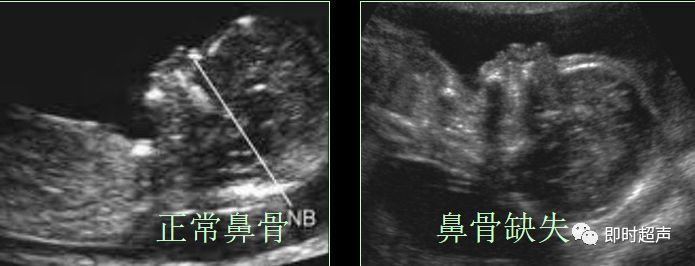

二、胎儿鼻骨(NB)

胎儿鼻骨于胚胎期第6周开始发育,9-11周通过膜性成骨方式骨化,正常胎儿中有1.4%的鼻骨存在缺失。

标准测量平面为胎儿水平位置正中矢状面,显示为鼻梁内的强回声细线。

鼻骨发育不良

NB筛查时间:11—14周,异常标准:鼻骨缺失、鼻骨短小是染色体异常的超声指标。

鼻骨长度

11-14W 3mm

20-24W 7mm

超声鼻骨切面:正中矢状切面和横切面诊断鼻骨缺失时,至少需要在 2 个互相垂直的切面印证。

超声检查胎儿鼻骨可作为产前超声筛查的一个有效指标。

超声检查鼻骨临床价值:11-14周胎儿鼻骨检查的成功率为95%。21-三体的胎儿60-70%鼻骨缺失,中孕期 DS 组胎儿的鼻骨缺失发生率为 55.5%,而正常对照组为0.5%。